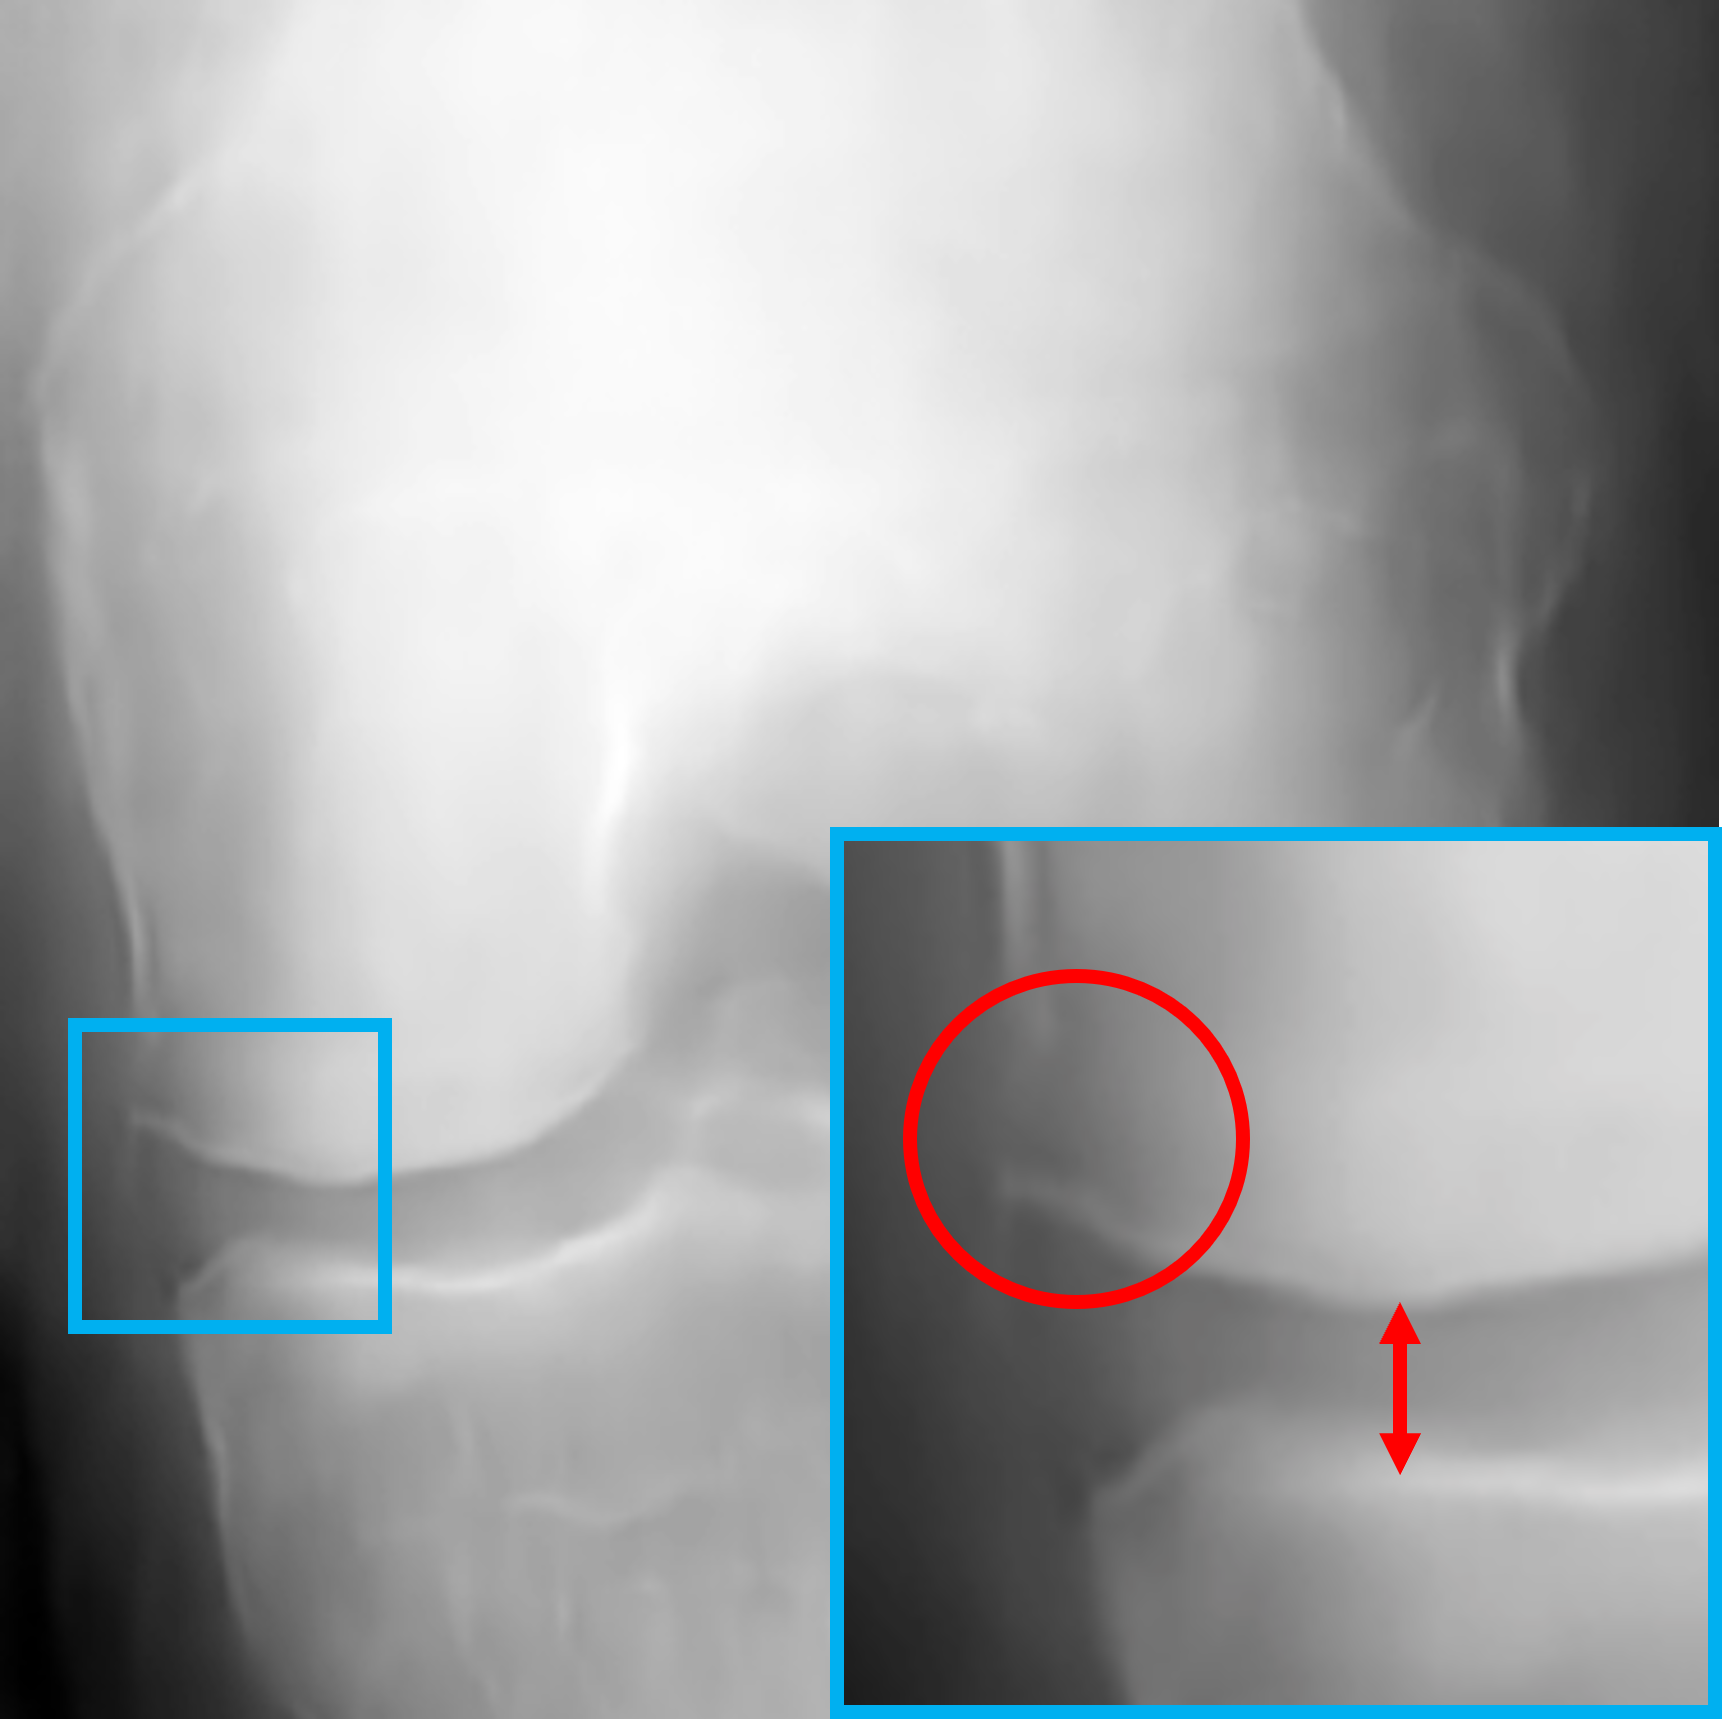

V-B Visualization of the feature vectors

To provide a more intuitive understanding of the proposed key feature exchange mechanism, we visualized the original inputs and their key-exchanged counterparts, as shown in Fig. 4. Specifically, X1subscript𝑋1X_{1}italic_X start_POSTSUBSCRIPT 1 end_POSTSUBSCRIPT (Fig. 4a), a KL-0 healthy knee X-ray, is contrasted with its key-exchanged output X1superscriptsubscript𝑋1X_{1}^{\prime}italic_X start_POSTSUBSCRIPT 1 end_POSTSUBSCRIPT start_POSTSUPERSCRIPT ′ end_POSTSUPERSCRIPT (Fig. 4b), while X2subscript𝑋2X_{2}italic_X start_POSTSUBSCRIPT 2 end_POSTSUBSCRIPT (Fig. 4c), a KL-2 osteoarthritic knee X-ray, is compared with X2superscriptsubscript𝑋2X_{2}^{\prime}italic_X start_POSTSUBSCRIPT 2 end_POSTSUBSCRIPT start_POSTSUPERSCRIPT ′ end_POSTSUPERSCRIPT (Fig. 4d). In X1subscriptsuperscript𝑋1X^{\prime}_{1}italic_X start_POSTSUPERSCRIPT ′ end_POSTSUPERSCRIPT start_POSTSUBSCRIPT 1 end_POSTSUBSCRIPT, pathological features associated with KL-2, JSN and osteophytes, are successfully introduced, while in X2subscriptsuperscript𝑋2X^{\prime}_{2}italic_X start_POSTSUPERSCRIPT ′ end_POSTSUPERSCRIPT start_POSTSUBSCRIPT 2 end_POSTSUBSCRIPT, these features are removed, restoring the joint space to resemble a healthy knee. It is noteworthy that, both X1subscriptsuperscript𝑋1X^{\prime}_{1}italic_X start_POSTSUPERSCRIPT ′ end_POSTSUPERSCRIPT start_POSTSUBSCRIPT 1 end_POSTSUBSCRIPT and X2subscriptsuperscript𝑋2X^{\prime}_{2}italic_X start_POSTSUPERSCRIPT ′ end_POSTSUPERSCRIPT start_POSTSUBSCRIPT 2 end_POSTSUBSCRIPT preserve the structural integrity and background details of the original images, demonstrating the model’s ability to selectively extract and modify key features without compromising realism. These visual results validate the effectiveness of our proposed global approach in separating key and non-key features, ensuring that the generated outputs are both diverse and valid. More details about the clinical validation will be discussed in Section V-E.

Refer to caption

(a) Original input X1subscript𝑋1X_{1}italic_X start_POSTSUBSCRIPT 1 end_POSTSUBSCRIPT (KL-0)

(b) key-exchanged output X1superscriptsubscript𝑋1X_{1}^{\prime}italic_X start_POSTSUBSCRIPT 1 end_POSTSUBSCRIPT start_POSTSUPERSCRIPT ′ end_POSTSUPERSCRIPT (KL-2)

(c) Original input X2subscript𝑋2X_{2}italic_X start_POSTSUBSCRIPT 2 end_POSTSUBSCRIPT (KL-2)

(d) Key-exchanged output X2superscriptsubscript𝑋2X_{2}^{\prime}italic_X start_POSTSUBSCRIPT 2 end_POSTSUBSCRIPT start_POSTSUPERSCRIPT ′ end_POSTSUPERSCRIPT (KL-0)

Figure 4: Highlighted illustration of the original inputs and key-exchanged outputs. The green and red colours represent the absence and presence of symptoms for osteophytes and JSN, respectively. The circles and arrows represent the possible positions of the osteophytes and JSN modification, respectively.